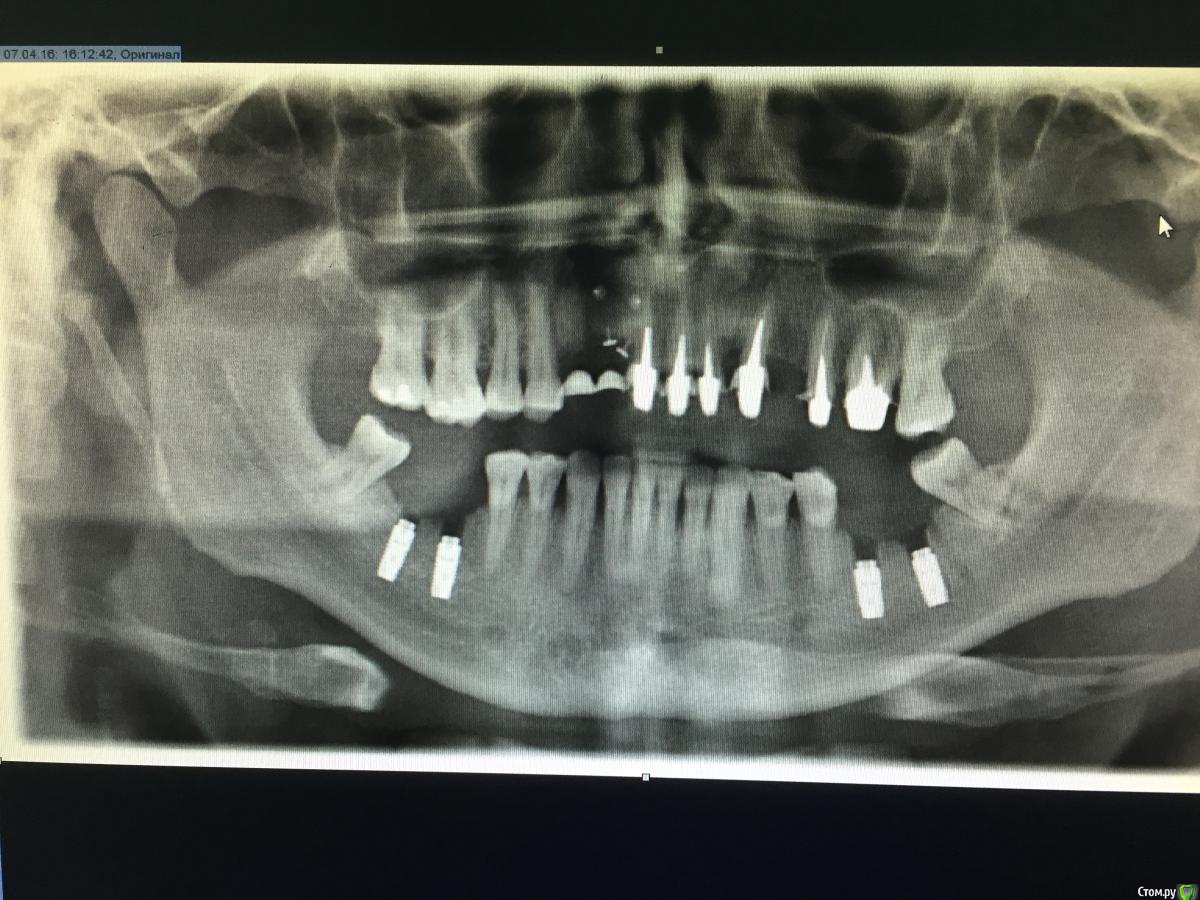

Тимур86 Опубликовано 12 апреля, 2016 Поделиться Опубликовано 12 апреля, 2016 Доктора!на сколько представляется возможным запротезировать эти имплантаты без вреда для пациента? Ссылка на комментарий

M@estro Опубликовано 12 апреля, 2016 Поделиться Опубликовано 12 апреля, 2016 Надо внушить хирургу ( включая ножевые ранения в живот) , что астра - не анкилоз, и так ставить ее, мягко говоря, неправильно. 5 Ссылка на комментарий

Тимур86 Опубликовано 13 апреля, 2016 Автор Поделиться Опубликовано 13 апреля, 2016 Соотношение имплант/коронка пугает.как бы винт не лопнул Ссылка на комментарий